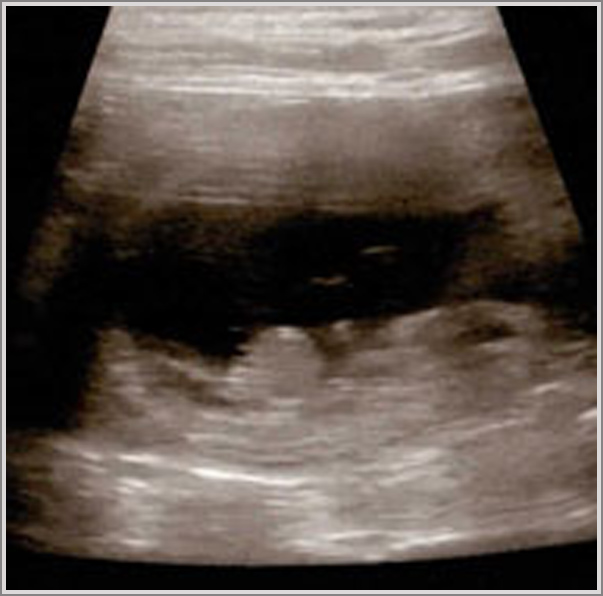

Bei der Sonographie (Ultraschall) kann man ab heute Herzbewegungen sehen.

Heute ist der beste Zeitpunkt, um die Trächtigkeit per Ultraschall nachzuweisen.

!!!JUHU Es hat geklappt Inara ist trächtig!!!

Ab heute kann eine Trächtigkeit per Ultraschall nachgewiesen werden.